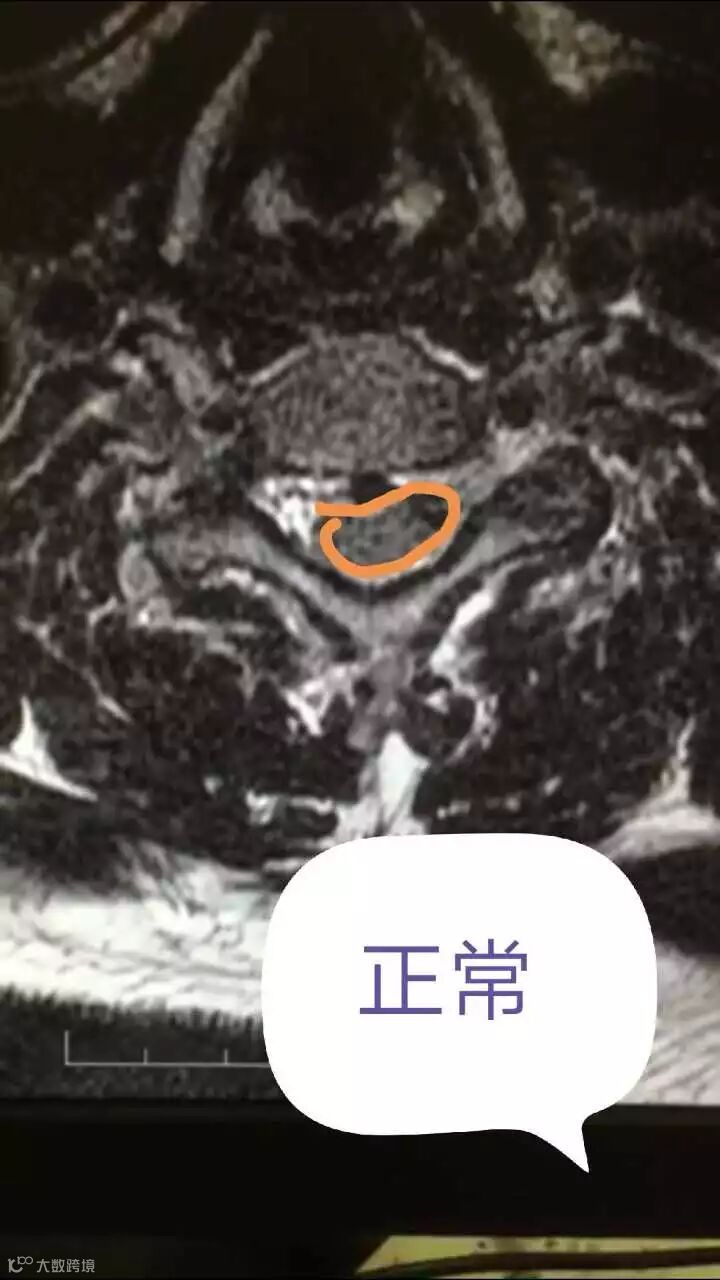

“检查发现,他的颈椎脊髓从椭圆形被压迫成月牙形,以至于影响到脊柱神经功能,小便无法解出,人处于不完全瘫痪状态。而在颈椎病突发患者中,因为坐火车导致发病如此之重的,这是我们遇到的第一例。”